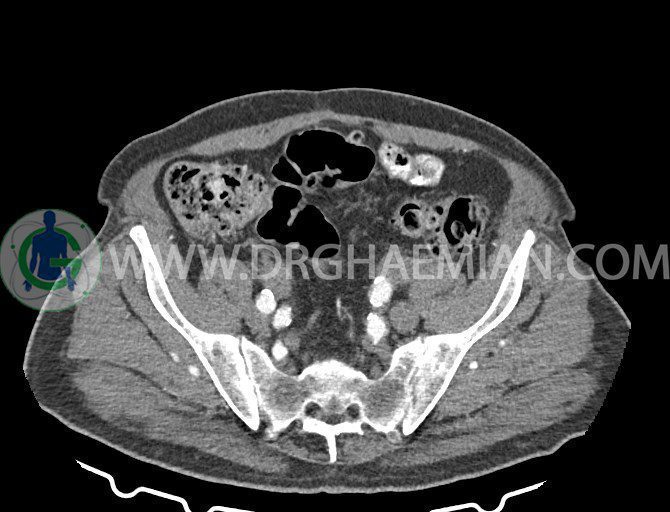

سی تی اسکن لگن یکی از روش های تصویربرداری با سی تی اسکن است. این روش با استفاده از تشعشعات تصاویر عرضی از ناحیه شکمی ایجاد میکند. در این کیس ديورتيكولوزيس، کیست های کورتیکال در هر دو کلیه، لنفادنوپاتی، کلسیفیکاسیون دیواره آئورت و شریان ایلیاک، تغییرات DJD ناحیه توراکولومبار و پروستات بزرگتر از عادی دیده می شود.

در سي تي اسکن اسپيرال شکم و لگن با و بدون کنتراست خوراکی و وريدی (مولتي ديدکتور 16 با مقاطع ظريف و بازسازي هاي ساژيتال و کرونال):

– کيست هاي کورتيکال ساده به قطر 5 mm تا 50 mm در کليه راست و به قطر 5mm تا 55 mm در کليه چپ

– توده ايزودنس به ابعاد mm 17 x 28 در پره ائورت مجاور قسمت تحتاني D3 دئودنوم مطرح کننده لنفادنوپاتي و با احتمال کمتر آنوريسم ترومبوزه (نيازمند مطابقت سونولوژيک)

– کلسيفيکاسيون ديواره آئورت و شريان ها ايلياک همراه با نشانه هاي ترومبوز مورال در بيفورکاسيون ائورت با امتداد به پروگزيمال هاي شريان هاي ايلياک

– ديورتيكولوزيس در کولون نزولي وسيگموئيد

لنفادنوپاتي به ابعاد mm 22 x 25 مجاور شريان ايلياک خارجي چپ و به ابعاد mm 17 x 28 مجاور شريان ايلياک خارجي راست

– تغييرات DJD در ناحيه توراکولومبار و

– پروستات به ابعاد mm 45 x 54، بزرگ تر از نرمال

مشهود است.